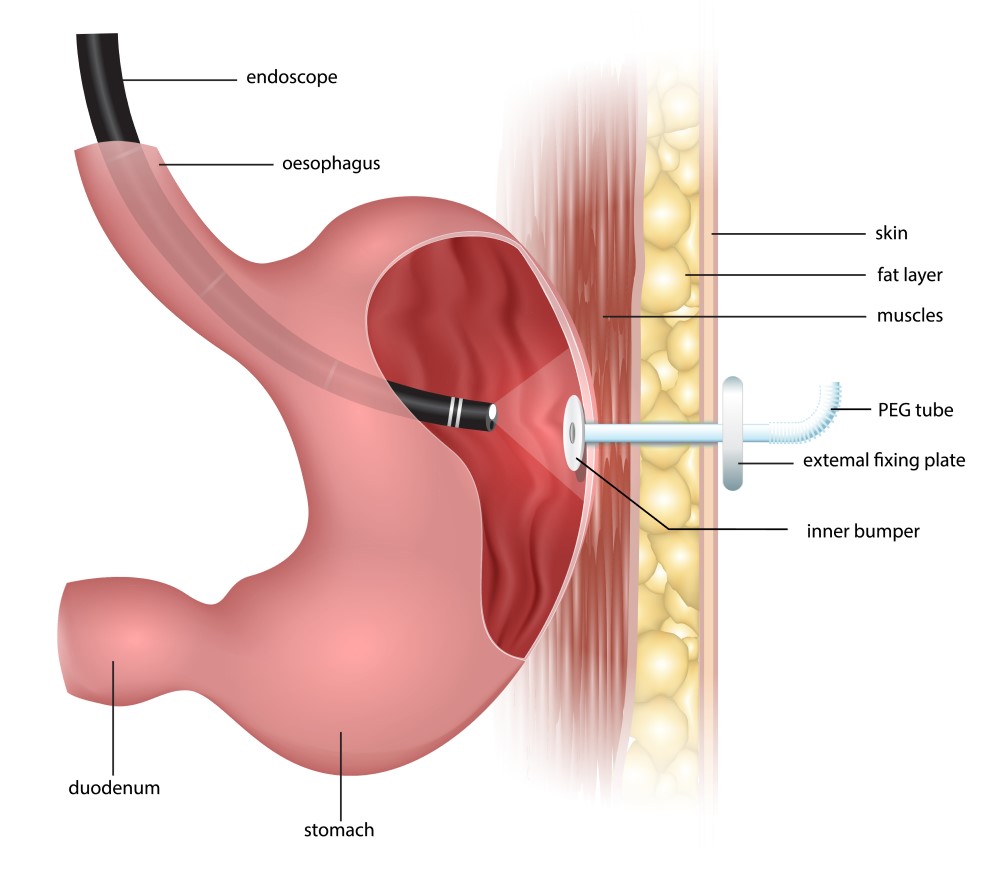

PEG PEJ Procedure Video Medical Video Library

PEG PEG 1 PEG PEG PEG

PEG PEG 1 PEG PEG 1 5cm

Care Of A PEG Feeding Tube Kent Community Health NHS Foundation Trust

1 PEG Point PEG PEG 24 48